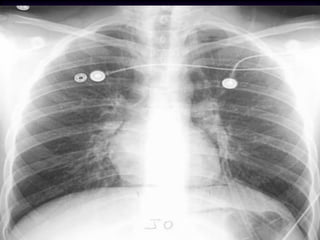

Adult Respiratory Distress Syndrome

Non-cardiogenic pulmonary edema

Distinguishing characteristics:

Normal size heart

No pleural effusion